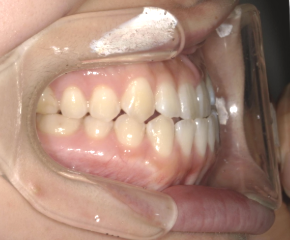

After Photo

After

主訴

かみ合わせ、反対咬合が気になる。

治療期間

9か月

料金

相談料0円、検査料33,000円、動的矯正治療費990,000円、保定装置料5,500円x2枚(必要枚数)

治療概要

前歯のかみ合わせが反対咬合だったため、下顎の歯を全体的に奥へ移動させ、前歯のかみ合わせを改善した。